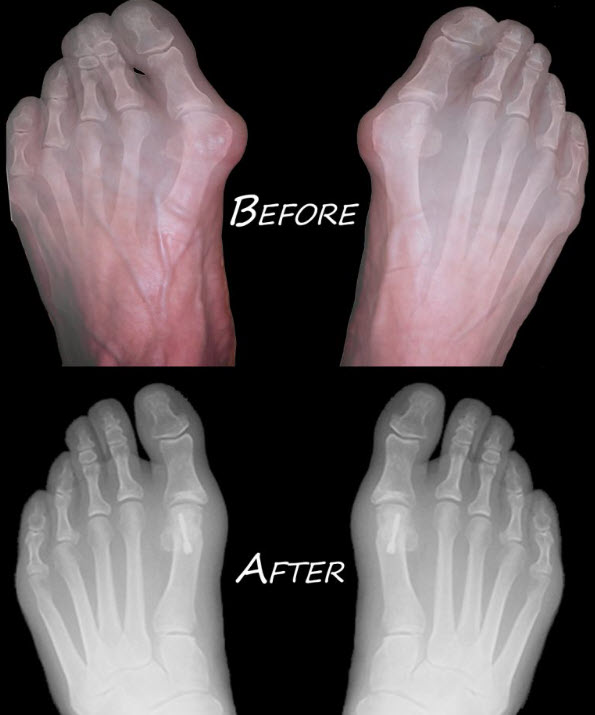

The symptoms and appearance of a bunion are often enough for a podiatrist to diagnose the condition. A physical examination of the foot and more information about a patient’s medical history and health will also help with the diagnosis. In some instances, a podiatrist may order an x-ray. The x-ray can be useful to help determine the severity of a bunion as it provides a clear image of the structures of the foot.

Because bunions result in deformity of the toe joint, surgery is usually the best option to correct the bunion and restore the joint and the foot to a more natural shape. Several surgical techniques and approaches can be used to correct a bunion. During the procedure, an incision will be made near or over the joint, and the joint will be placed in its normal position and secured with pins or screws. A portion of bone may also need to be removed to enable the joint position to be properly restored. In some cases, the joint may be fused to keep it properly aligned with the rest of the foot. Swollen tissue may also be removed during the procedure.

Before and After – Bunion Treatment at Global Podiatry